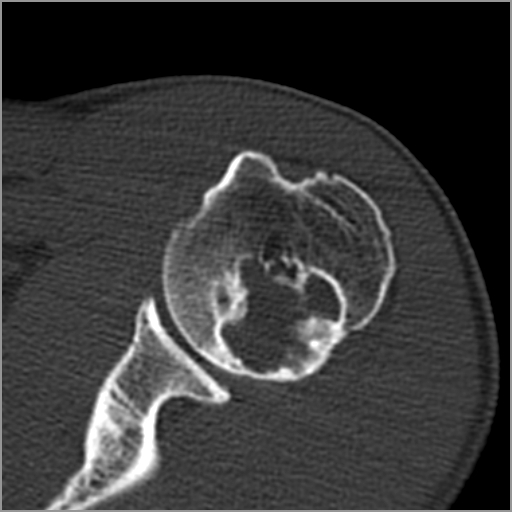

以下是引用zxd95在2008-7-19 18:45:00的发言:[br]囊性病灶边缘硬化、皮质变薄但连续——提示生长时间长、良性病变——考虑左肱骨头骨囊肿。[br]

以下是引用杀毒软件在2008-7-19 18:55:00的发言:[br]考虑:骨巨细胞瘤可能性大